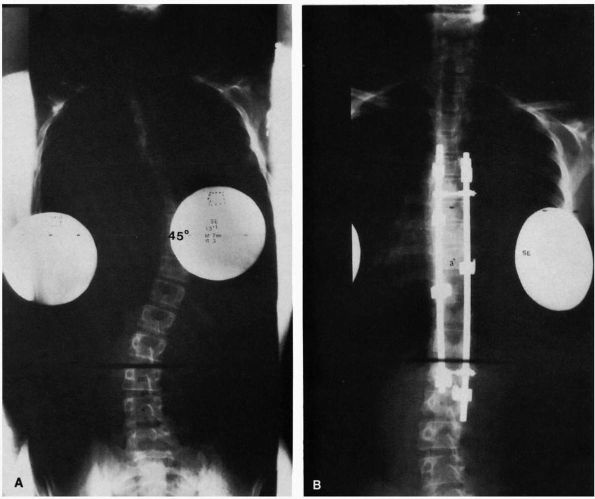

FIGURE 16-14. (A) Thirteenyear, 1-month-old girl with a curve that progressed from 23 to 45° despite bracing. (B) After spinal fusion and Cotrel-Dubousset instrumentation, the same patient’s curve measures 3°.

|